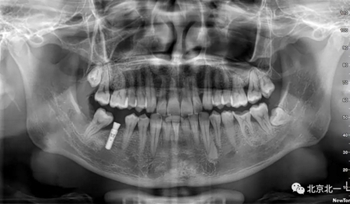

術(shù)后拍片。

正畸支抗直立47

第一次支抗釘脫落, 第二次支抗釘位于48位置, 頰側(cè)舌側(cè)舌側(cè)扣牽引。